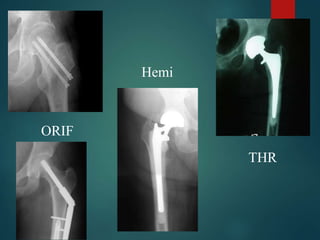

Femoral Neck Fractures

 Treatment Options

 Non-operative

 Very limited role

 Activity modification

 Skeletal traction

 Operative

 ORIF

 Hemiarthroplasty (Endoprosthesis)

 Total Hip Replacement

ORIF

Hemi

THR

 Young Patients

 Urgent ORIF (<6hrs)

 Elderly Patients

 ORIF possible (higher risk AVN, non-union, and failure of fixation)

 Hemiarthroplasty